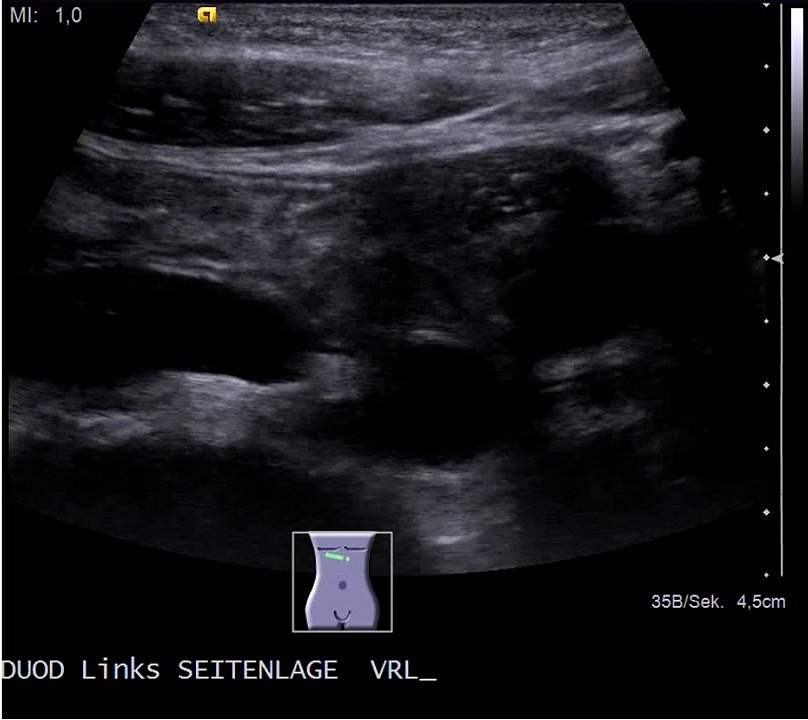

Wilkie Syndrom: Entleerung des Duodenums in Linksseitenlage

Duodenum nach Nahrungsaufnahme bei Wilkie-Syndrom: Widerstandsperistaltik